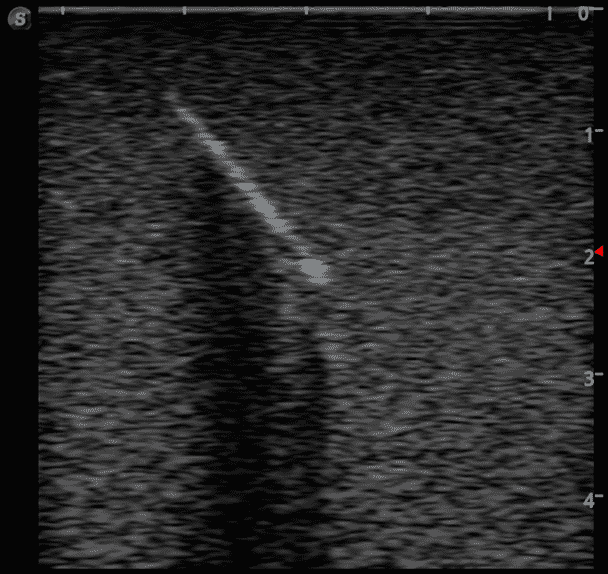

This training block is designed for training users in the techniques associated with ultrasound guided foreign body identification, targeting, and retrieval.

· High-quality ultrasound images

· Different object depths for various training

· Objects found in the human body including:

Glass shards

Wood splinter

Bullet

Plastic fragments

Metal fragments